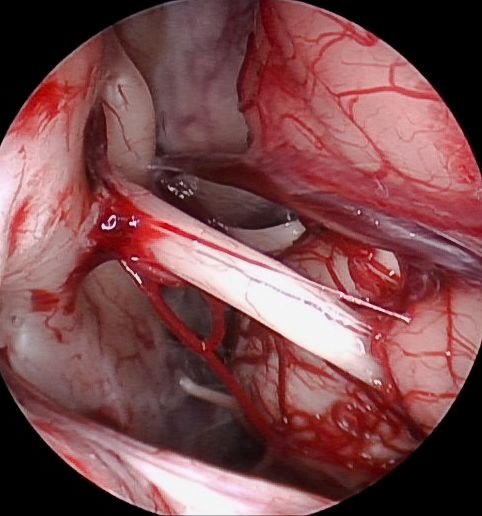

Durch die Einführung der fluoreszenzgestützten Resektion wurden bedeutende Fortschritte in der operativen Therapie bösartiger Hirntumoren erzielt. Vor dem Eingriff erhält die Patientin oder der Patient etwa vier Stunden vor der Operation eine Trinklösung (Gliolan®). Das enthaltene Medikament wird in den bösartigen Tumorzellen in einen Fluoreszenzfarbstoff umgewandelt. Während der Operation kann der Operateur durch spezielle Beleuchtung (Blaulicht) den Fluoreszenzfarbstoff anregen und den Tumor sichtbar machen. Diese Technik ermöglicht eine präzisere Tumorresektion und trägt somit maßgeblich zu einer verbesserten Prognose der betroffenen Patientinnen und Patienten bei.